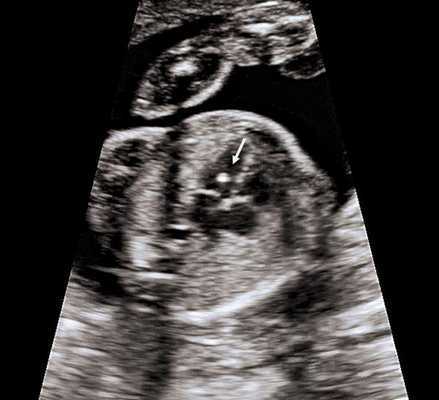

Рис. 1. Увеличение толщины воротникового пространства

В основной группе численные значения расширенного воротникового пространства плода варьировали от 2,5 до 11,0 мм и превышали соответствующие показатели (5-й, 50-й, 95-й центиль) в группе сравнения в 11-12, 12-13 и 13-14 недель беременности (рис. 1).

Изображение воротникового пространства можно оценивать как с помощью трансабдоминального, так и трансвагинального сканирования. Оценка ТВП у плода проводится при значениях копчико-теменного размера (КТР плода) от 45 до 84 мм и позволяет заподозрить хромосомные аномалии, особенно трисомию 21-й хромосомы (синдром Дауна) и сформировать среди беременных группу риска по рождению детей с врожденной и наследственной патологией.

Толщина воротникового пространства (ТВП) на УЗИ